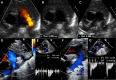

The patent ductus arteriosus is a very common condition in preterm infants, and a hemodynamically significant patent ductus arteriosus increases morbidity and mortality in these vulnerable patients. However, despite numerous randomized controlled trials, there is no consensus regarding management. Medical therapy is typically offered as first-line treatment, although it yields limited success and carries the potential for severe adverse events. In recent years, there has been rapid development in transcatheter patent ductus arteriosus closure primary with the use of the Amplatzer Piccolo Occluder, and this has gained widespread acceptance as a safe and effective alternative to surgical ligation in extremely low-birth-weight infants weighing over 700 g. This article aims to provide an appraisal of the patient selection process, a step-by-step procedural guide, and a comprehensive review of the outcomes associated with this approach.